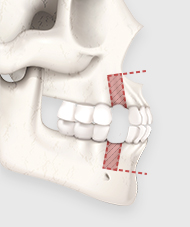

잇몸뼈와 치아를 전체적으로

후방으로 이동시켜

입이 튀어나온 인상을 개선하고,

얼굴 옆선의 조화를 찾는 수술입니다.

작은 어금니를 발치한 뒤, 위아래 잇몸뼈를 삭제합니다.

제거된 치아와 잇몸뼈만큼 턱뼈를 뒤쪽으로 이동시켜 과도한 돌출 증상을 해소합니다.

돌출입 수술은 단순히 돌출된 입을 밀어 넣는 것이 아니라,

코 끝부터 인중, 입술을 거쳐 턱 끝까지

자연스러운 라인을 완성하는 것이 핵심입니다.

코 끝과 인중, 입술과 턱 끝, 그리고 치아 각도까지 고려하여

입체적인 얼굴 옆 라인을 완성합니다.